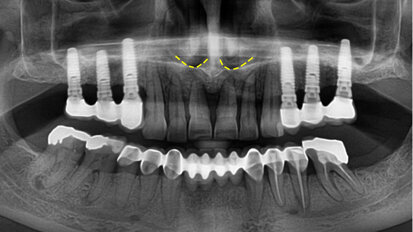

Nepřímá metoda pro ošetřování prostřednictvím provizorií

Týmový přístup při celkové hybridní rekonstrukci.